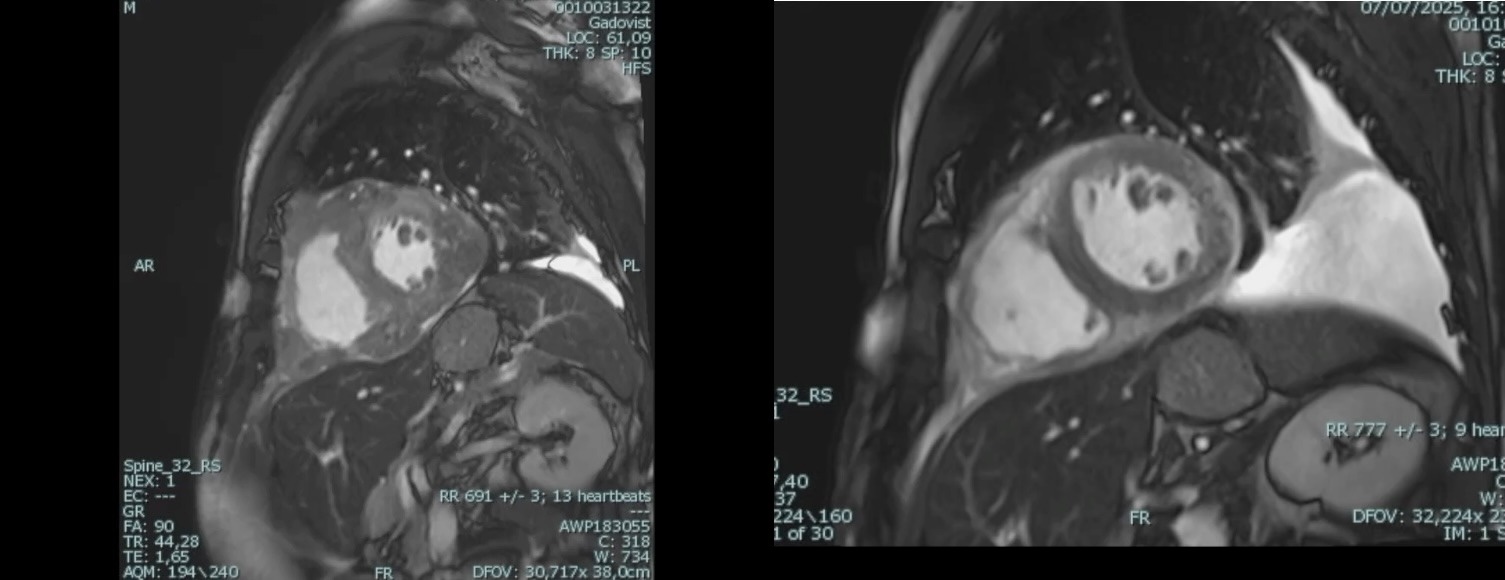

Background Primary cardiac lymphoma is an extremely rare condition, accounting for less than 0.5% of extranodal lymphomas. It can present with a variety of symptoms, including pericardial effusion, heart failure, arrhythmias, or coronary artery compression. Accurate diagnosis requires a multimodal imaging approach—utilizing echocardiography, cardiac magnetic resonance (CMR), and PET-CT—complemented by cytological or histological confirmation. Case Description A 62-year-old male with a history of B-cell lymphoma presented to the Emergency Department with pleuritic chest pain and pericardial and pleural effusions. Despite initial treatment for suspected pericarditis with colchicine and ibuprofen, the patient’s condition progressed to hemodynamic compromise, requiring pericardiocentesis. Cytologic analysis and a supraclavicular mass biopsy confirmed recurrence of high-grade B-cell non-Hodgkin lymphoma. PET-CT imaging showed systemic spread with significant cardiac and pleural uptake. During hospitalization, the patient developed hypoxemia, hypotension, and acute chest pain. CT angiography excluded embolism but identified extrinsic compression of the right pulmonary artery. Concurrently, ECG changes and new regional wall motion abnormalities (posterolateral hypokinesia) appeared, with a decline in left ventricular ejection fraction (LVEF). Coronary angiography demonstrated critical stenoses of the left anterior descending, intermediate, and circumflex arteries, all suggestive of extrinsic compression. CMR further confirmed extensive intramyocardial infiltration. Following the failure of first-line Polatuzumab-Rituximab, second-line therapy with Obinutuzumab and Glofitamab was initiated. This targeted approach led to progressive lesion regression, normalization of ventricular function (LVEF improved from 38% to 56%), and complete resolution of the coronary stenoses. Conclusions This case highlights the importance of considering cardiac lymphoma in the differential diagnosis of recurrent pericardial effusion, unexplained ventricular dysfunction, or atypical coronary stenoses, particularly in patients with a history of lymphoproliferative disease. Integrating advanced imaging with histological confirmation is essential for diagnosis and targeted immunochemotherapy. These therapies can effectively induce mass regression and complete functional cardiac recovery, including the resolution of extrinsic vascular compression.